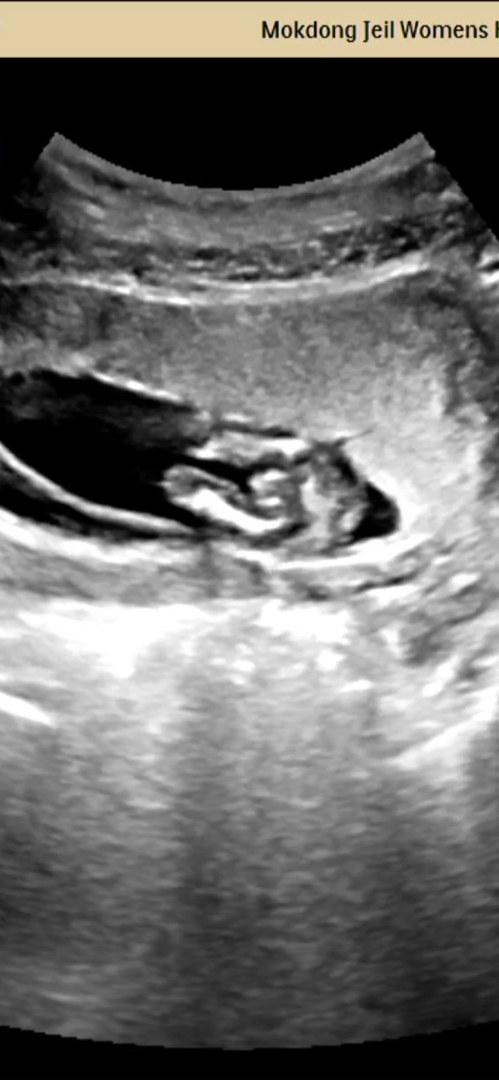

14주치곤 확실한 것 같은뎅..ㅎㅎㅎㅎ

그 유명한 삼각점 맞나요....????ㅋㅋㅋㅋㅋㅋㅋ 선생님은 아직 있다가도 없어지는 시기라고 하셨는데...( 14주 2일) 저 봐버린거 맞죠...?ㅋㅋㅋㅋㅋㅋㅋ👼🏻

우왕.. 삼각점 아니구 미사일인데요?😆 귀여워라 ㅠㅠㅠㅎㅎㅎ

ㅋㅋㅋㅋㅋ맞는것같아요ㅋㅋ 존재감 뿜뿜